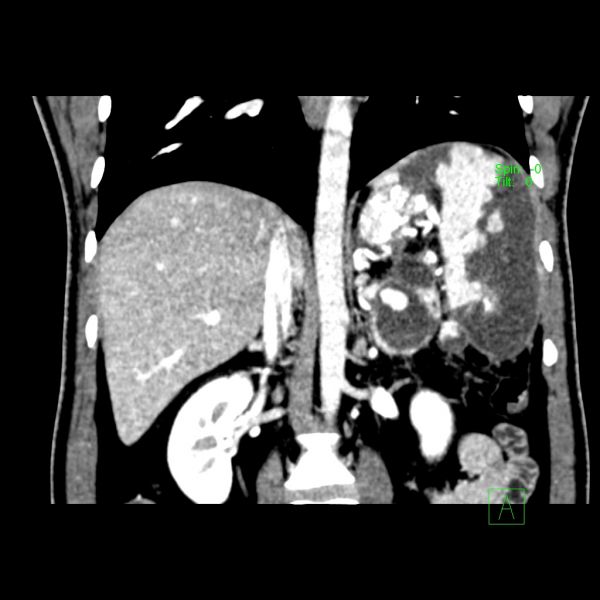

患者入院时CT提示:坏死性胰腺炎、合并假性囊肿形成、假性脾动脉瘤、左门脉高压症、脾梗死。病情紧急,且情况不容乐观。

时间就是生命,救治刻不容缓。肝胆外科一病区通过详细评估后,对病情的复杂性和术中风险有了充分准备。该患者集坏死性胰腺炎、合并假性囊肿形成、假性脾动脉瘤、左门脉高压症、脾梗死于一体,对医生的医术是一大考验,且术中极易发生大出血,不易控制。但胸有成竹的王文儿主任经过全科室术前讨论后,当即决定在患者入院的第二天进行急诊手术。历时4个多小时的生死赛跑,王文儿主任带领的肝胆外科一病区手术团队成功完成了这台“胰腺体尾部切除+胰腺假性囊肿剥除+脾脏切除术”的复杂急诊手术。术中仅出血300ml,术后患者恢复顺利,症状完全缓解,2周即康复出院。

术前CT